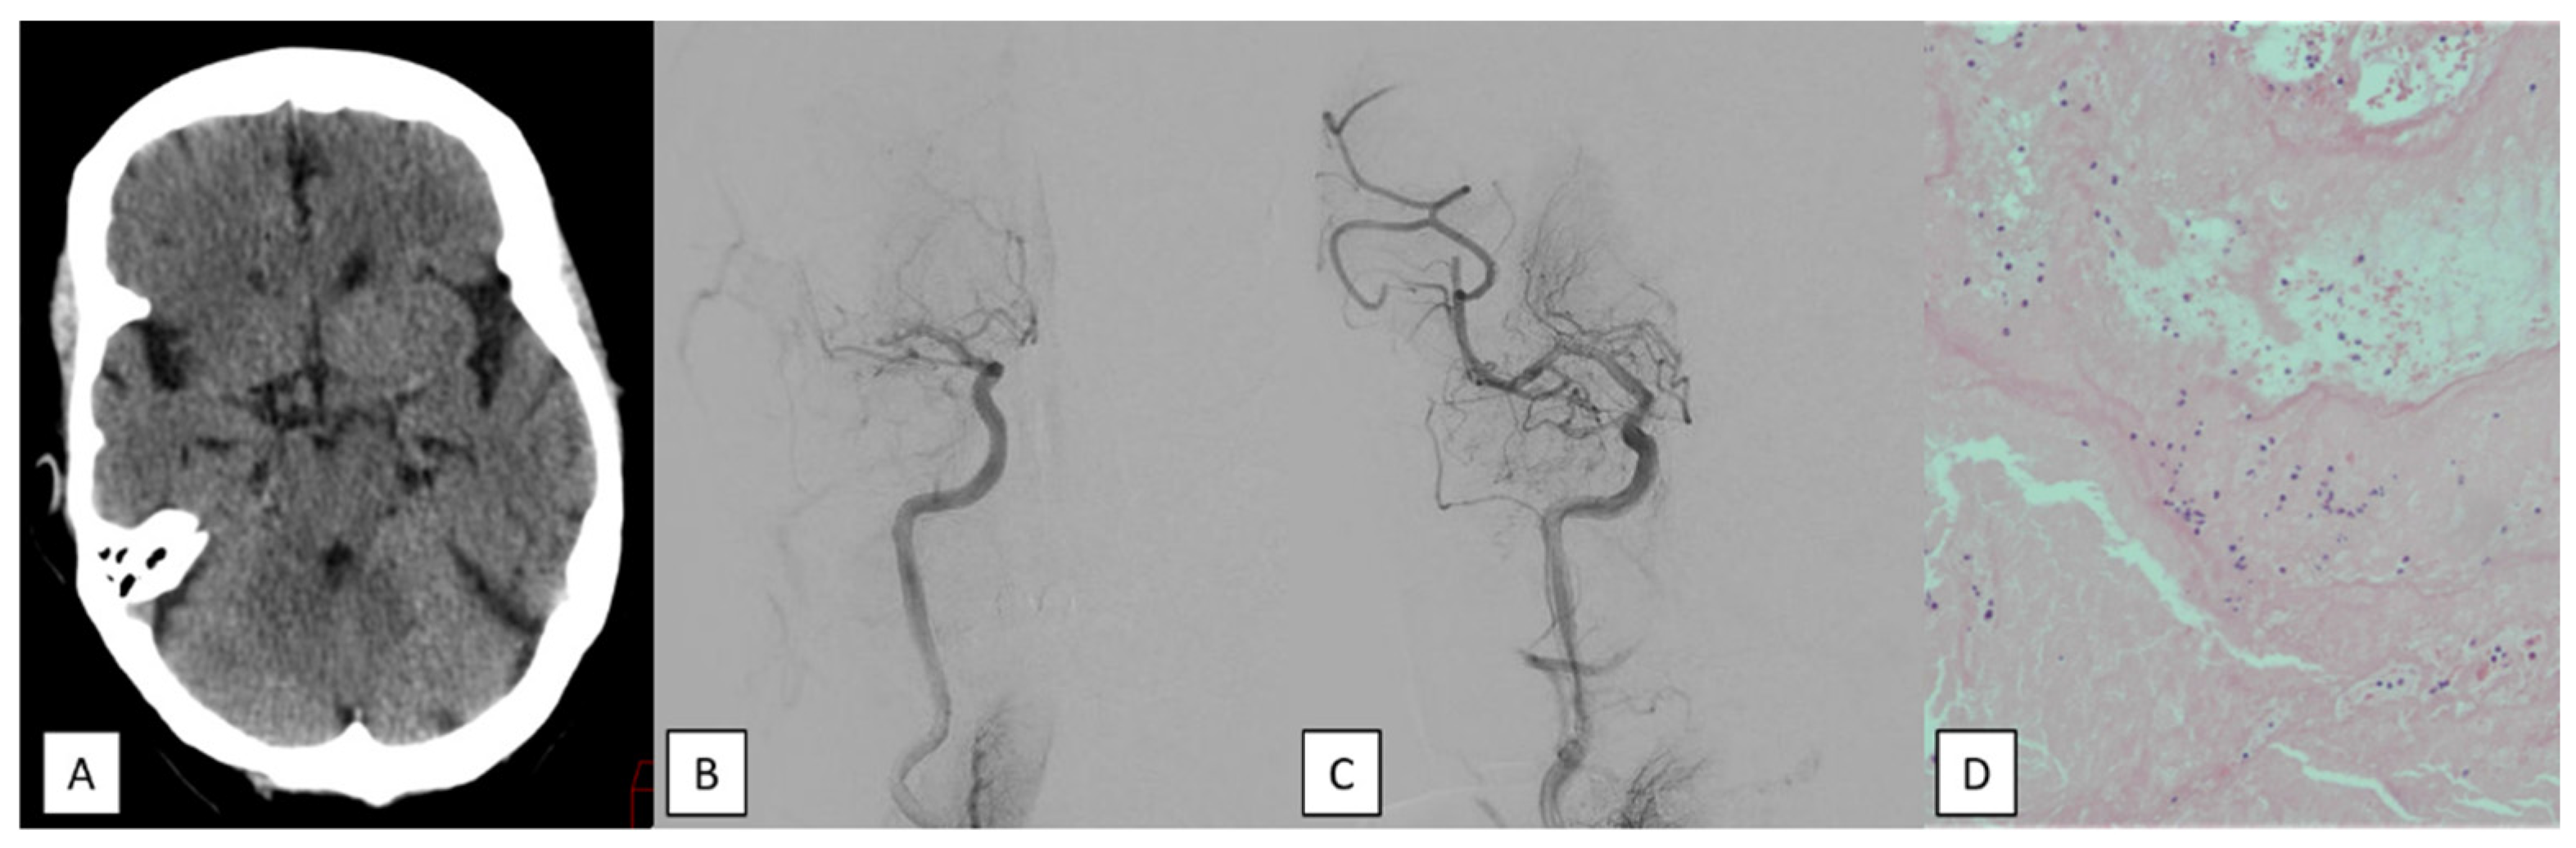

- Underlying intracranial stenosis. A severe (70–99%) residual stenosis and/or in situ thrombosis with reocclusion on repeat angiographies.

- Clot hardness/burden. A resistance to extraction despite correct device placement and the concomitant existence of a predominant fibrinoplatelet or calcium clot.

- Red, fibrine, and mixed clots: A red clot occurs when the percentage of red blood cells is ≥60%. A fibrin-predominant clot is identified when the ratio of fibrin to platelet is ≥60%. A mixed clot is present if there is no clear predominance of these components.

- Septic clots: These occur when there is an increased number of white blood cells exhibiting morphological alterations. To detect bacteria, the slide was examined at 100× magnification (scale bar, 10 μm) using immersion oil.

- Calcium clots: a major component of calcified tissue.

- Fatty clots: an accumulation of adipose tissue as the major component.